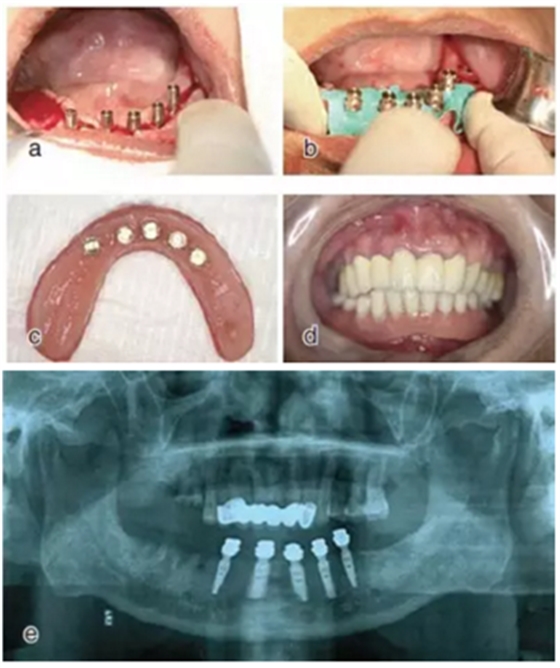

翻瓣種植

設(shè)計(jì)切口,剝離黏骨膜后,將截骨導(dǎo)板戴到骨面上,用咬骨鉗沿著截骨導(dǎo)板平面進(jìn)行截骨,并用骨銼修整骨平面,截骨完成后將種植導(dǎo)板固定在骨面上進(jìn)行種植備孔,完成后植入種植體。注意截骨平面要平整,否則影響種植導(dǎo)板的就位。

圖17 截骨與備孔:a.戴上截骨導(dǎo)板后進(jìn)行截骨并修平骨面;b. 戴上種植導(dǎo)板進(jìn)行備孔

種植后修復(fù)

戴上套筒冠基臺進(jìn)行即刻修復(fù)。注意不是所有植入的種植體都可以進(jìn)行即刻修復(fù),醫(yī)師可以通過扭力值并結(jié)合ISQ松動度測量值來選擇修復(fù)的種植體。

圖18 進(jìn)行即刻修復(fù):a.戴上基臺;b.在基臺上戴入套筒冠;c. 套筒冠固位到原有義齒上;d.患者戴上有套筒冠的覆蓋義齒;e. 即刻修復(fù)完成后曲面體層片